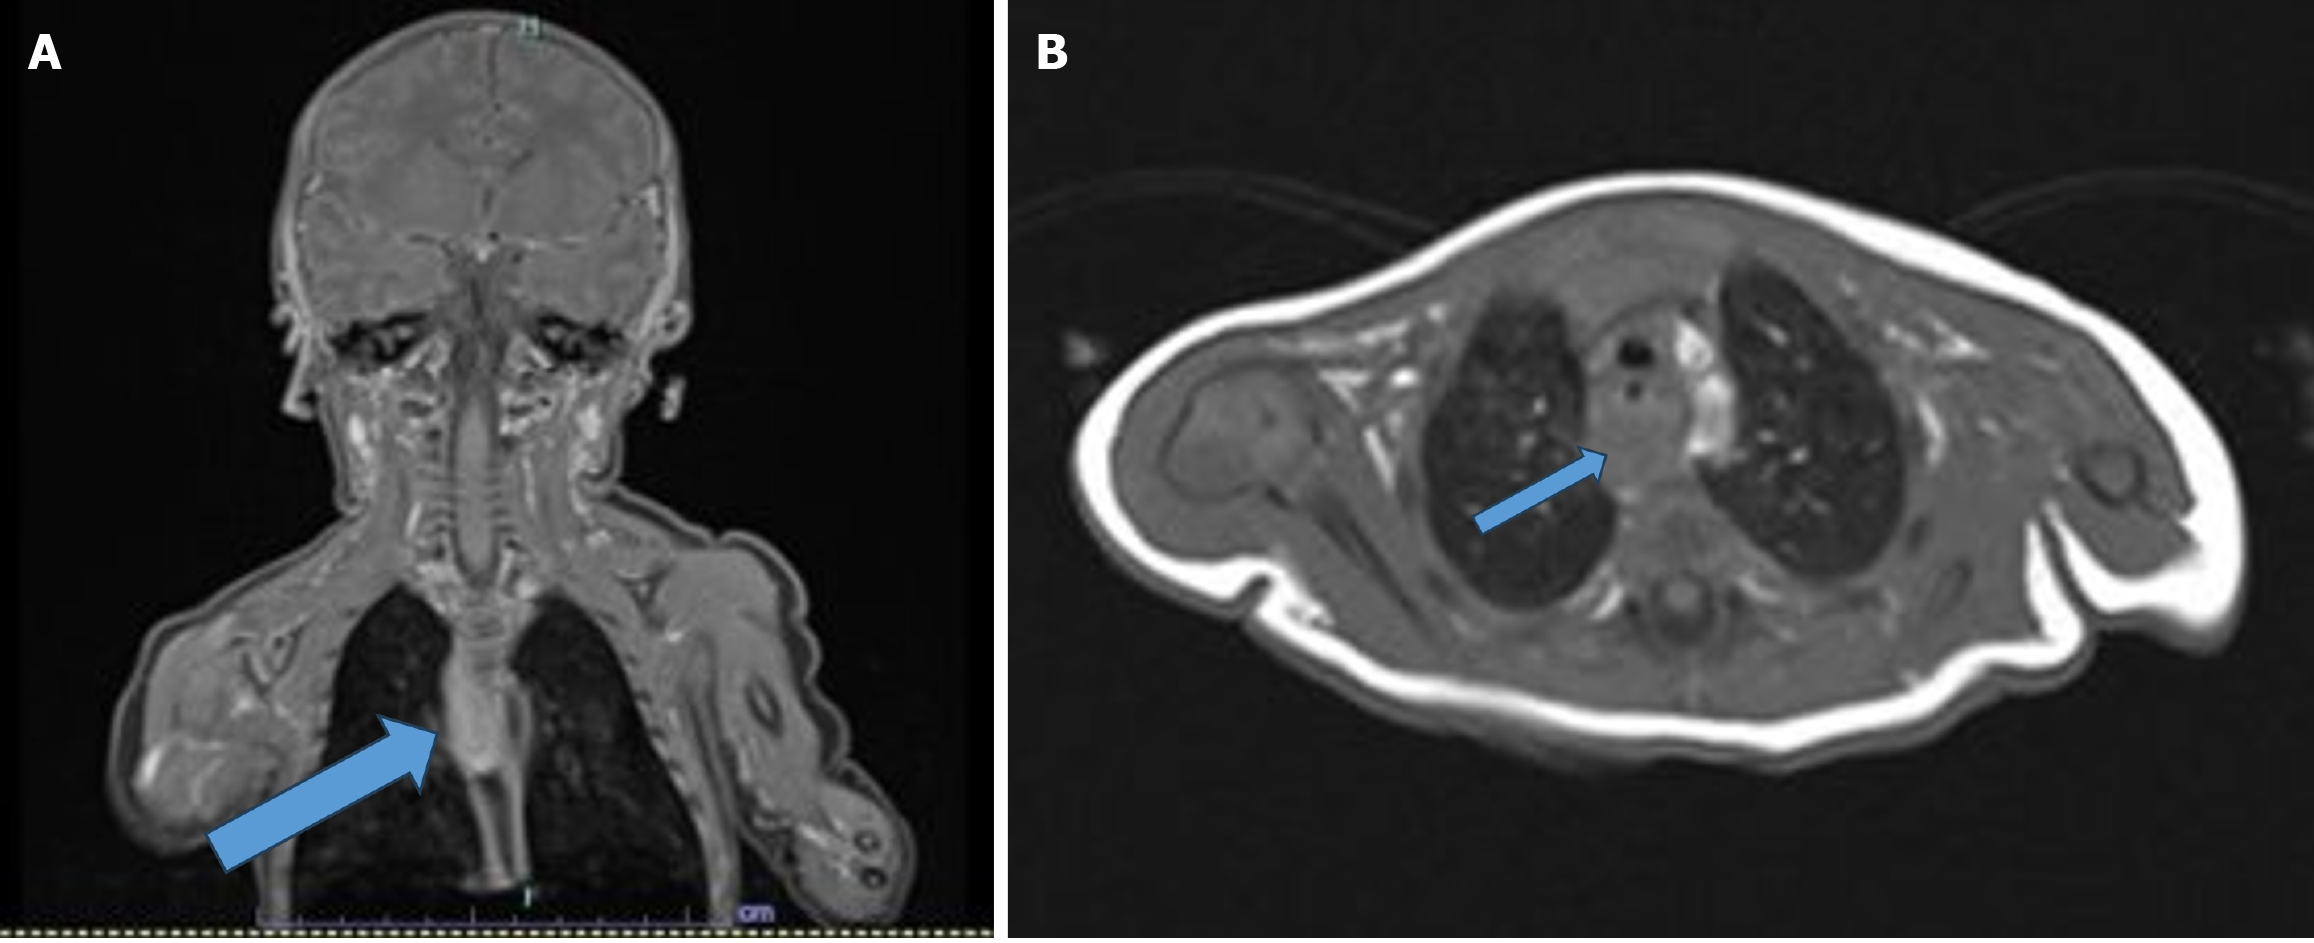

A fiber-optic airway examination showed no abnormalities. However, a neck magnetic resonance imaging, while normal in the cervical region, raised suspicion for a mass in the posterior upper mediastinum (Figure 2).